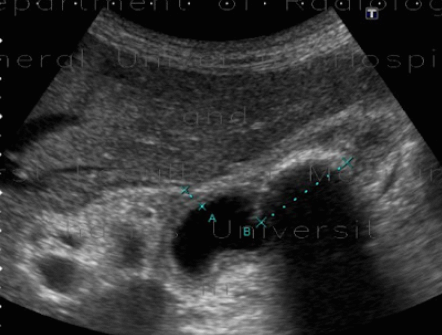

US finding

- 담낭이 비대해지고 담낭벽이 비후 된다

- 담낭 내 격막이 있다